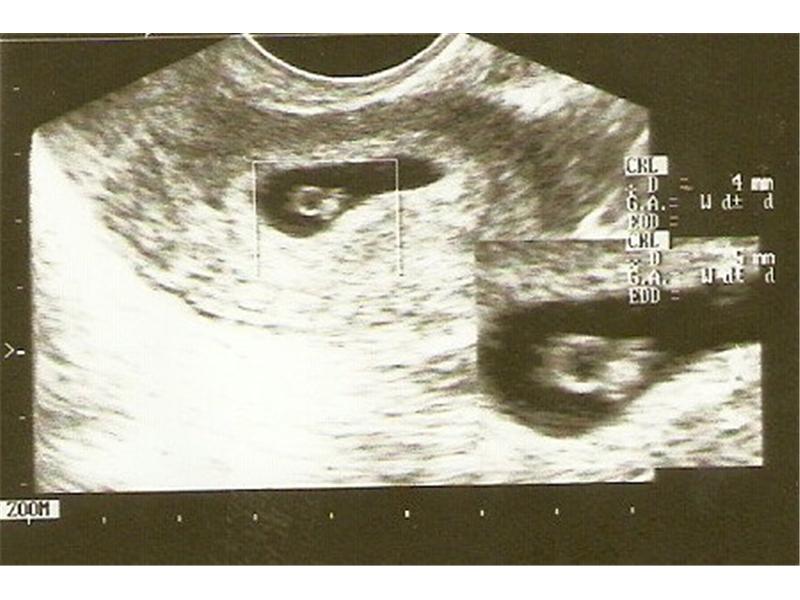

Bublinka

1.miminko